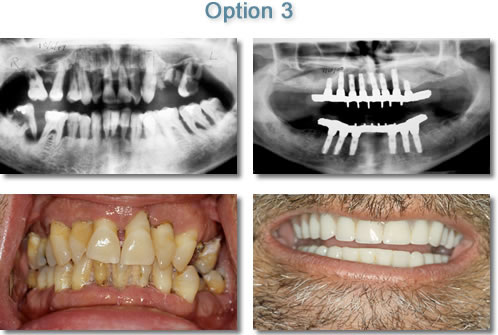

Maxillary & Mandibular Completely Elentulous Fixed Hybrid Prosthesis

Option 3: Hybrid Prosthesis A hybrid or fixed-detachable prosthesis is a combination of an implant-supported overdenture and an implant supported fixed bridge. Four to six implants are usually used and prosthesis is screwed or cemented onto the implants. The prosthesis is removable by your dentist but cannot be taken out by the patient. This option is often used when the patient states, "I don't want to remove my teeth."